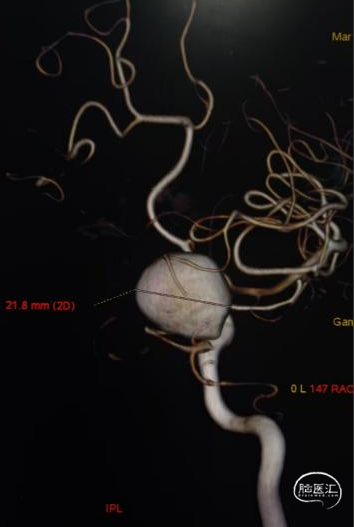

术前影像

脑动脉DSA提示右侧颈内动脉C5床突段动脉瘤。

右侧床突段载瘤动脉远端血管直径为1.8mm,载瘤动脉近端血管直径为5.2mm,瘤体宽13.1mm,瘤体最大宽度21.8mm。